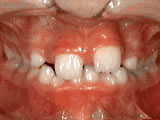

Crowding of the teeth

crowning of teeth

Before

Patient started treatment at age 11 and wore braces for 26 months. He loves his new smile.